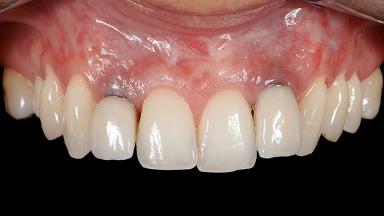

Periodontal Plastic Surgery and Prosthetic Procedures to Treat Peri-Implant Soft-Tissue Dehiscences

A 30-year-old woman was referred by her general dentist for evaluation of an esthetic complication related to previous implant treatment for congenitally missing maxillary lateral incisors. The patient’s chief complaint was the inadequate esthetic appearance of her smile. The case demonstrates the use of a combined approach to achieve optimal results. Two different flap designs - a tunnel technique and a coronally advanced flap - are employed based on the surgical objectives for the affected site.